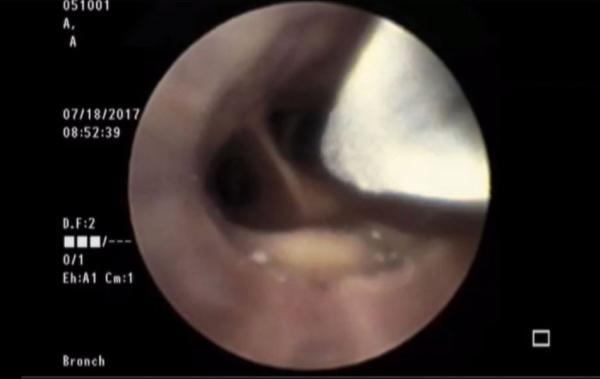

In a procedure called Bronchial RheoplastyTM a non-thermal pulsed electrical field is used to ablate the epithelium of the airways to improve symptoms for patients with chronic bronchitis.

Based on lung anatomy, the RejuvenAir System delivers metered CryoSprays of liquid nitrogen through a bronchoscope under direct visualization.